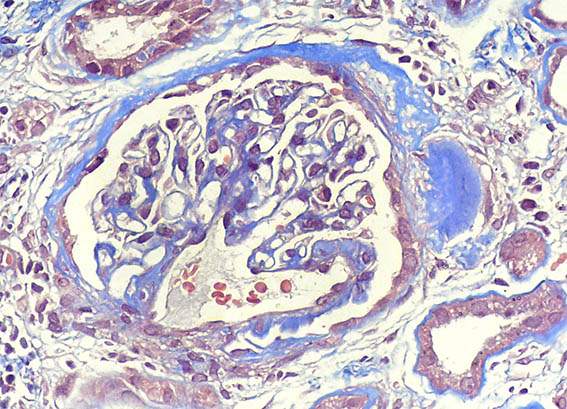

Figura 1.

Tricrómico de Masso, X200.